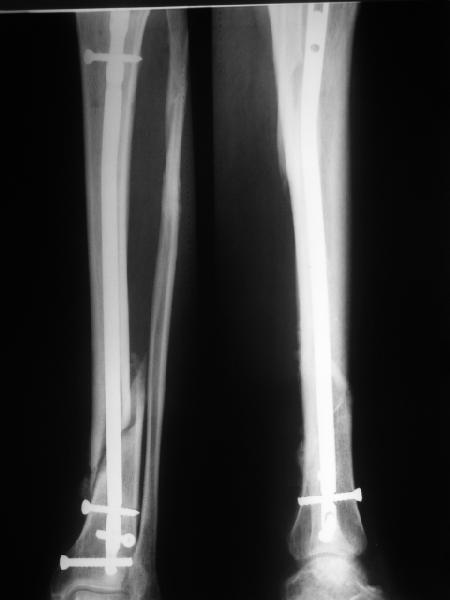

Большинство коллег высказалось против реостеосинтеза и представленные снимки этому подтверждение-данный кососпиральный перелом репонируется идеально только открыто,что при БИОС не так существенно.

Здесь проблема не в идеальности репозиции, а в запасе усталостной прочности. Срастаться там может небыстро, диастазы довольно большие.

И когда еще и отломок короткий, и отверстие совсем рядом, это может привести к перелому стержня. За последние годы у нас было несколько пациентов, оперированных в других учреждениях с

подобным положением отломков, с такими переломами гвздей. И сейчас переделать куда как проще и легче, чем иметь дело со сломанным гвоздем.

Антон, дорогой, важнее вальгуса тут близость верхнего отверстия к перелому и отсутствие уверенности в быстром сращении из-за большого

диастаза.

В Кемпбелле можно прочитать, что Fractures in the distal third of the tibia had the highest frequency of nail breakage.

Вообще, этот вопрос обсуждался давно, и еще в статье R. Bucholz (1987) про переломы гвоздей указывалось, что расстояние от ближайшего отверстия до перелома должно быть не менее 5 см, иначе есть угроза усталостного перелома. По литературе переломы гвоздей в нижней трети

tibia достигают 4,3%.